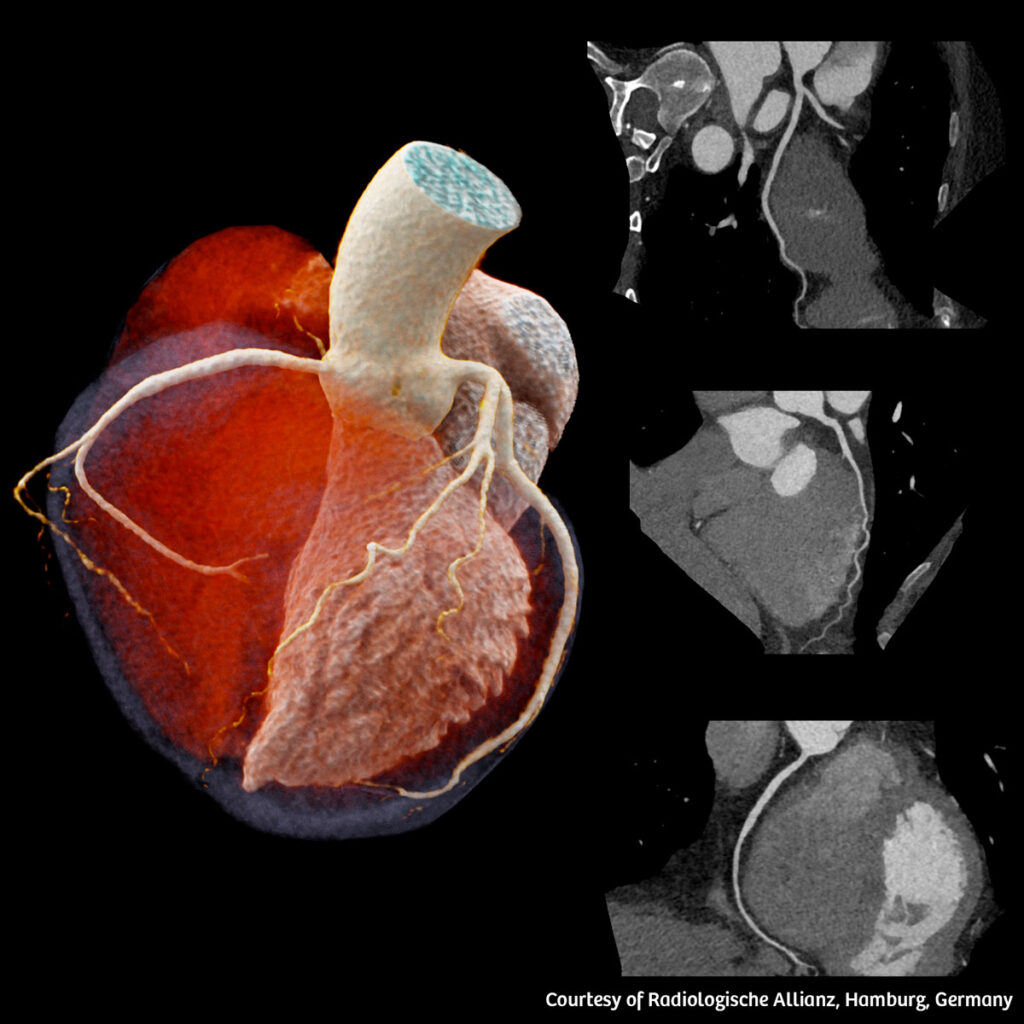

Dual Source computed tomography – CT scanners with two radiation tubes and detectors each – allows for very high temporal resolution. High temporal resolution and scan speed is important for CT scans of the heart, to limit image artifacts from breathing or motion of the heart. This enables scanning patients with various challenging clinical conditions, such as patients with high or irregular heart rates, inability to hold their breath or to stay still, as well as with difficulties following clinicians’ instructions. The use of tin filters keeps the radiation dose low while maintaining optimum image quality especially in clinical indications like ultra-low dose thorax scans for screening.